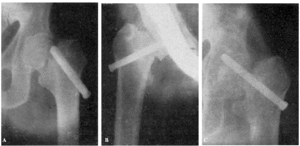

Fracaso número 2(observación número 2). F. S., setenta años4. Ingresa en el servicio con una fractura mediana del cuello femoral izquierdo. Osteosíntesis extraarticular (fig. 3. A y B). La impactación no ha resultado perfecta.

Figura 3. A: obs. núm. 2. El clavo no penetra suficientemente y la impactación, salvo en la parte superior de la línea de fractura, es muy defectuosa. B: obs. núm. 2. La posición del clavo es buena. C: obs. núm. 2. El clavo tiende a ser expulsado hacia fuera y apenas penetra en la cabeza femoral.

A los veinte días de la intervención pasa el enfermo a su domicilio, recomendándole que continúe en la cama. Pasado un mes vemos nuevamente al enfermo, el cual nos manifiesta que anda con mucha más dificultad que en los primeros días de permanecer en su domicilio, que fue cuando, por no haber interpretado bien nuestras indicaciones, comenzó a emprender la marcha. La radiografía (fig. 3. C) demuestra que el clavo apenas penetra en la cabeza femoral. A los ocho días hacemos otra radiografía (fig. 4. A), observándose que el trocáncer ha ascendido, a pesar de continuar guardando cama el enfermo. Ingresa nuevamente en el servicio, donde, con anestesia raquídea, retiramos el clavo, reduciendo las fracturas y volviendo a colocar un clavo más largo en buena dirección (fig. 4. B). Una radiografía practicada siete años y medio más tarde demuestra la no consolidación de la fractura, trastornos tróficos en cuello y cabeza femoral y que el cabo ha penetrado en el fondo de la cavidad cotiloidea, en donde ha labrado una cavidad (fig. 4. C).

Figura 4. A: obs. núm. 2. El trocánter ha ascendido francamente con relación a la radiografía anterior. El clavo tiende a salir de la cabeza por su parte superior. B: obs. núm. 2. Se extrajo el clavo y se colocó otro. El nuevo clavo está colocado en buena dirección, pero la reducción no es perfecta. C: obs. núm. 2. El clavo ha penetrado en el fondo de la cavidad cotiloidea, en cuyo lugar ha labrado una cavidad. Trastornos tróficos en cuello ycabeza femoral. El cuello del fémur ha desaparecido casi completamente.

En este caso el fracaso se debe a que la impactación no fue perfecta, y sobre todo, a haber el enfermo iniciado la deambulación al mes de intervenido, a pesar de que nosotros le ordenamos que guardara cama.